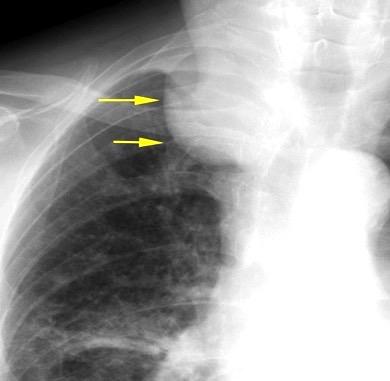

Síntomas y signos que se producen con la obstrucción total o parcial de la vena cava superior

Causas Malignas +/- 90-95%

Ca. Broncogénico (80-85%)

Linfoma No Hodgkin (15%)

Catéteres, shunts y marcapasos…23%

T. Mediastínico. Bocio

Fibrosis Idiopática

Tb, Histoplasmosis, Actinomicosis, Sarcoidosis

Carcinoma microcítico con síndrome de VCS

Grupos:

1. Obstrucción por encima de la V Ácigos. (La sangre llega al corazón a través de ella)

2. Obstrucción con participación de la V. Ácigos. (La sangre utiliza otras alternativas para llegar al corazón vía VCI).

Participación de la V. Ácigos como vía principal para llegar a la VCI.

Visible: 88%